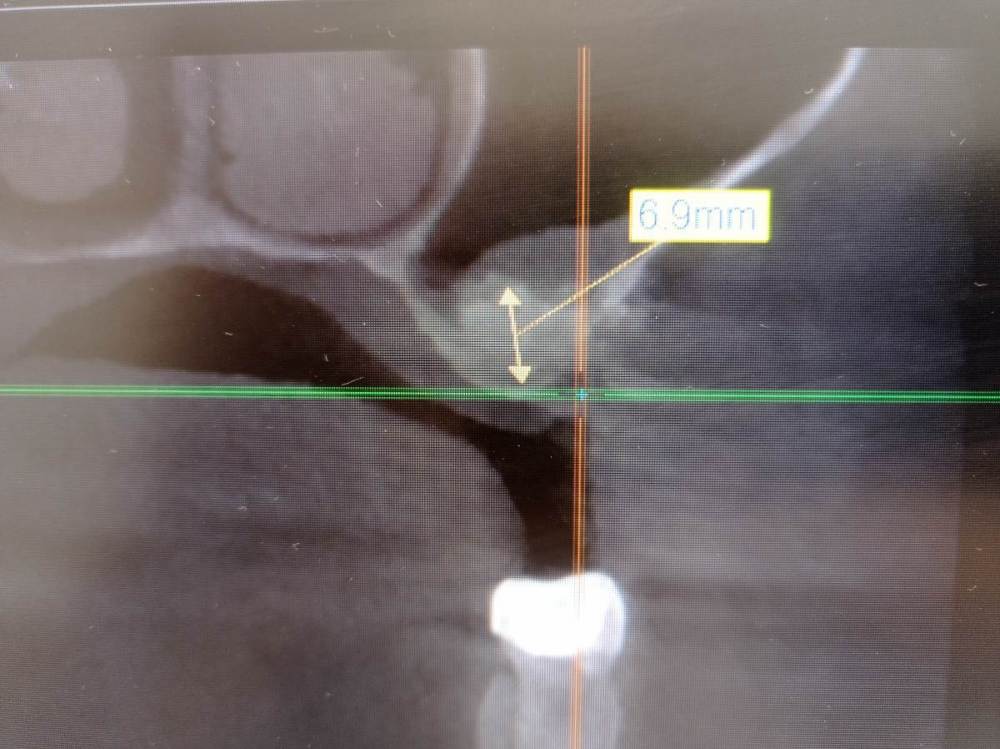

fog7 Опубликовано 5 февраля, 2024 Поделиться Опубликовано 5 февраля, 2024 Добрый день, коллеги, полгода назад был проведён осл, материла было уложено достаточно, перфораций мембраны во время операции не наблюдалось, послеоперационный период без осложнений. В итоге на клкт такая картина. Собираюсь добить зсл и поставить имплантат на 8мм. Скажите, как ведёт себя мембрана после осл, насколько высок риск перфораций? Ссылка на комментарий

fog7 Опубликовано 5 февраля, 2024 Автор Поделиться Опубликовано 5 февраля, 2024 Использовался Biooss s в чистом виде, контрольного клкт непосредственно после операции не проводилось Ссылка на комментарий

Женька Опубликовано 5 февраля, 2024 Поделиться Опубликовано 5 февраля, 2024 (изменено) Отвечая на Ваш вопрос, пусть коллеги меня поправят, но я вообще никаких проблем для ЗСЛ после ОСЛ не вижу. Я думал Bio-Oss выглядит на КЛКТ несколько более светлым) как все ксенографты. За полгода на ровном месте и при достаточном объёме, как Вы говорите, и вот так осталось, что-то не сходится Изменено 5 февраля, 2024 пользователем Женька Ссылка на комментарий

kramer Опубликовано 5 февраля, 2024 Поделиться Опубликовано 5 февраля, 2024 (изменено) 3 часа назад, fog7 сказал: Использовался Biooss s в чистом виде Чистый биоосс в пазухе почти не дает усадку. Либо часть графта ушла в пазуху, либо исходно столько и было. Думаю, можно спокойно сделать ЗСЛ Вот здесь было 2 шприца Bio Oss 0,5 L: Изменено 5 февраля, 2024 пользователем kramer 2 Ссылка на комментарий

fog7 Опубликовано 6 февраля, 2024 Автор Поделиться Опубликовано 6 февраля, 2024 Я больше склоняюсь к тому, что причина в не диагностированной перфорации, но это уже история. На сегодняшний момент актуально мнение коллег, как ведёт себя слизистая пазухи при повторных вмешательствах на ней, становится ли она более тонкой, менее прочной, насколько её возможно поднять мм на 3 без риска перфораций? Ссылка на комментарий